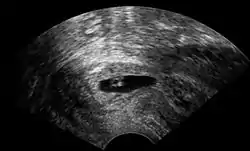

![]() تصوير بالموجات فوق الصوتية المهبلية لحمل عنقي في عمر 5 أسابيع من الحمل . انظر الصورة أدناه للحصول على تفاصيل الهياكل المرئية تصوير بالموجات فوق الصوتية المهبلية لحمل عنقي في عمر 5 أسابيع من الحمل . انظر الصورة أدناه للحصول على تفاصيل الهياكل المرئية | |

يتم التشخيص في النساء الحوامل بلا الأعراض إما عن طريق رؤية عنق رحم مزرق اللون، أو الأكثر شيوعا، عن طريق التصوير بالموجات فوق الصوتية التوليدية. العرض النمطي غير المحدد هو النزيف المهبلي أثناء الحمل. ستظهر الموجات فوق الصوتية موضع كيس الحمل في عنق الرحم، في حين أن تجويف الرحم "فارغ". يمكن الخلط بين حمل عنق الرحم والإجهاض عند مرور نسيج الحمل عبر عنق الرحم.